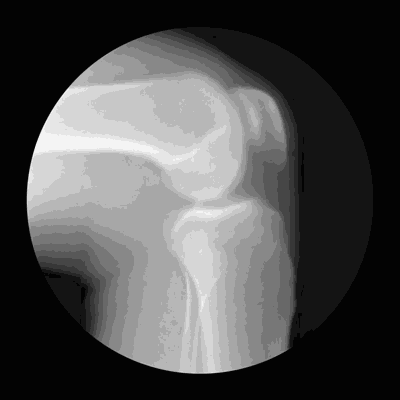

骨科医生: 半月板损伤的大都由运动引起 患者主要是年轻人 “实际上,二三十岁的年轻人确实是半月板损伤的主要人群。”浙江大学医学院附属第一医院骨科林向进主任医师在采访中告诉记者,这是因为,半月板损伤大部分都是由运动引起,年轻人运动较为活跃,受伤的也就多。 而老年人的半月板损伤多是在退变的基础上反复轻微的损伤造成的。有些家庭妇女可能出现半月板损伤,比如经常趴在地上擦地板,姿势不对,频繁刺激半月板,损伤渐渐累积,半月板超负荷“工作”时间久了,便会加重到撕裂程度的损伤。 半月板是膝关节内的新月状(C型)纤维软骨结构,有缓冲作用,可以稳定膝关节,减轻膝关节负荷压力。膝盖疼痛、肿胀、发出响声等,是半月板损伤的典型症状。 医生说道,“突然间的剧烈运动,最容易导致半月板损伤,特别是足球、羽毛球这两项运动,因为在运动时膝关节有一个旋转的动作,半月板也会随之运动,发生伤害。”他接诊过最年轻的半月板损伤患者才十几岁,是个小男孩,跟同伴追逐打闹的时候,腿扭了一下,半月板出现撕裂,需要手术治疗。 半月板损伤程度较轻的,仅部分撕裂的,临床症状又比较轻时可以保守治疗,急性期注意休息,局部理疗热敷,加强股四头肌的锻炼。临床症状改善后,在运动方式上要当心。如果半月板全程撕裂了或者撕裂程度影响了日常生活的,需要手术。林向进介绍,目前半月板手术都是膝关节镜下的日间微创手术,当天做好就能回家。 手术后还能不能运动了?答案是可以。“运动员做了半月板手术后,大多可以重返赛场的。”打羽毛球时一记大力扣杀 落地时膝盖一阵剧痛后走不了路 半月板损伤的44岁周先生正试着与半月板损伤“和平共处”。 周先生平时喜欢运动,跑步、爬山、踢足球,9年前,他开始喜欢上打羽毛球,一周2次,每次2小时,风雨无阻。 3年前,一次打羽毛球时,周先生一记大力扣杀,落地时感觉右腿膝盖一阵剧痛,之后痛到连路都走不了,只能由同伴搀扶着离开。 过了几天,疼痛还是没有消散,周先生去医院骨科就诊,核磁共振提示:半月板损伤。 “当时医生说,我的半月板损伤程度,可以选择保守治疗,当然也可以选择手术。我想了想,选择了先进行药物保守治疗。” 停不下来的周先生,之后还是陆陆续续打羽毛球,2年前,他的左膝盖也出现了问题,被诊断为半月板撕裂。 “急性发作的时候,膝盖痛得上下楼都困难。”周先生说道,“好在经过慢慢调养,现在不影响日常生活,但偶尔也还是会有不舒服。” 如今,周先生偶尔还是会打球,但他更加注重防护,打球前做好充分的拉伸准备,运动时戴上护膝,“像我们不是专业运动员,下肢力量不是特别足,羽毛球是急转急停的运动,如果准备不充分很容易受伤。”大二时做了半月板手术 20多年过去了还能跑马拉松踢足球 “我在大二那年做了半月板手术,到现在20多年过去了,感觉没有什么影响,每年跑马拉松,踢足球,我甚至都忘记是左膝盖还是右膝盖做了手术。” 杭州的夏先生曾是一名专业运动员,他回忆,自己半月板受伤,最早可能要追溯到初三。 有一次跳马训练,落地的姿势有点失控,小腿和大腿可能有些错位,但一直没有出现明显的疼痛症状。 五年后,夏先生读大二,一次跑步训练时,膝盖突然肿痛得厉害,脚不能沾地,一碰就痛。熬不住,去医院检查,核磁共振做出来,半月板损伤严重。在医生的建议下,夏先生进行了半月板手术。 手术后,夏先生休养了一年,第二年,他照样参加全国田径比赛,没有受到手术影响。 现在,距离手术过去20多年了,跑马拉松、踢足球,夏先生依然可以做自己喜欢的运动。 “当时给我手术的医生就说,我年纪轻,做完手术不影响今后的运动功能,现在看来,确实还没有受到太大的影响。很幸运。”夏先生说道。